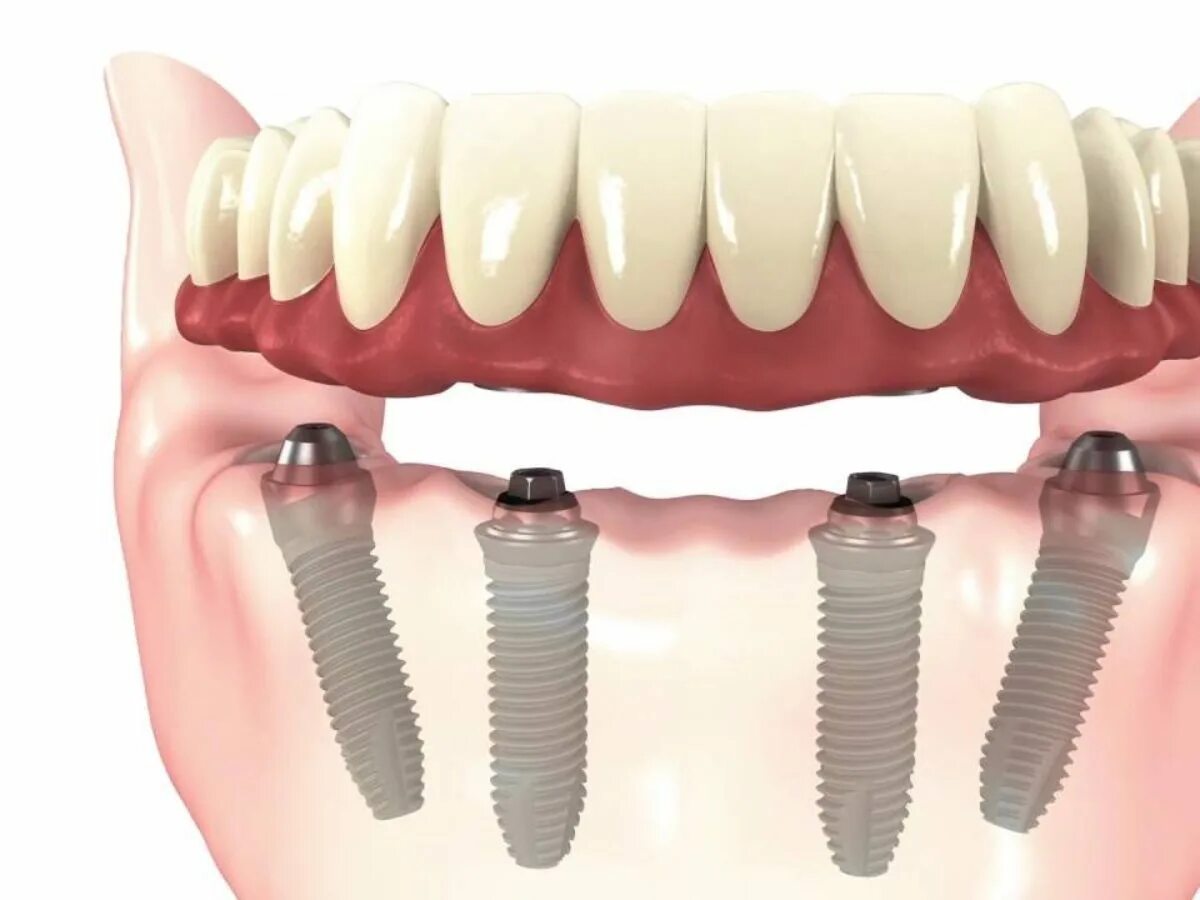

Ол он 4